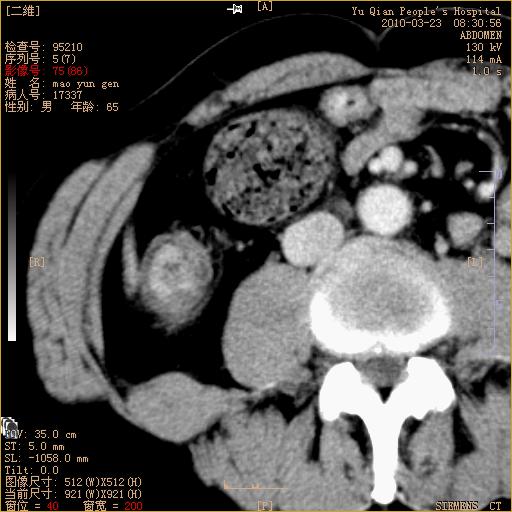

标题: CT25266:消瘦月余,前来肝部检查,请看看肠腔 [打印本页]

标题: CT25266:消瘦月余,前来肝部检查,请看看肠腔

升结肠肠壁增厚,不均强化,考虑升结肠腺癌可能性,建议肠镜检查。

1)考虑升结肠癌。2)右肾小囊肿。